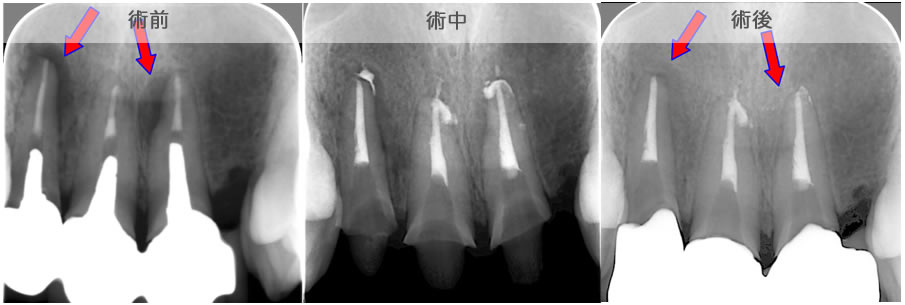

頬側骨壁の根尖部まで無くなっています。

MTA根充後11ヶ月で透過像が消失し、根尖部が正常化しました。

頬側骨の喪失が見られましたが17ヶ月で回復しました。

頬側骨の回復が確認できます。

| 治療説明 | 左下第一小臼歯の頬側根尖部からの排膿、痛みはないそうです。X線画像では根尖部に透過像を認められます。 頬側の骨も失われており、歯髄が死んだことが原因と考えられます。修復物を除去後根管治療を行い、根管充填後、透過像は消失、頬側骨も再生されていました。 |

|---|---|

| 治療期間 | 6〜24ヶ月 |

| 治療費用 | 150,000〜300,000円 |

| 治療に伴うリスク | 根管内からの治療で根尖病巣が治らない場合は、外科的に根尖病巣を除去する必要があります。 再根管治療を繰り返す場合、歯根の厚みが薄くなり、歯根破折のリスクが高まります。 |